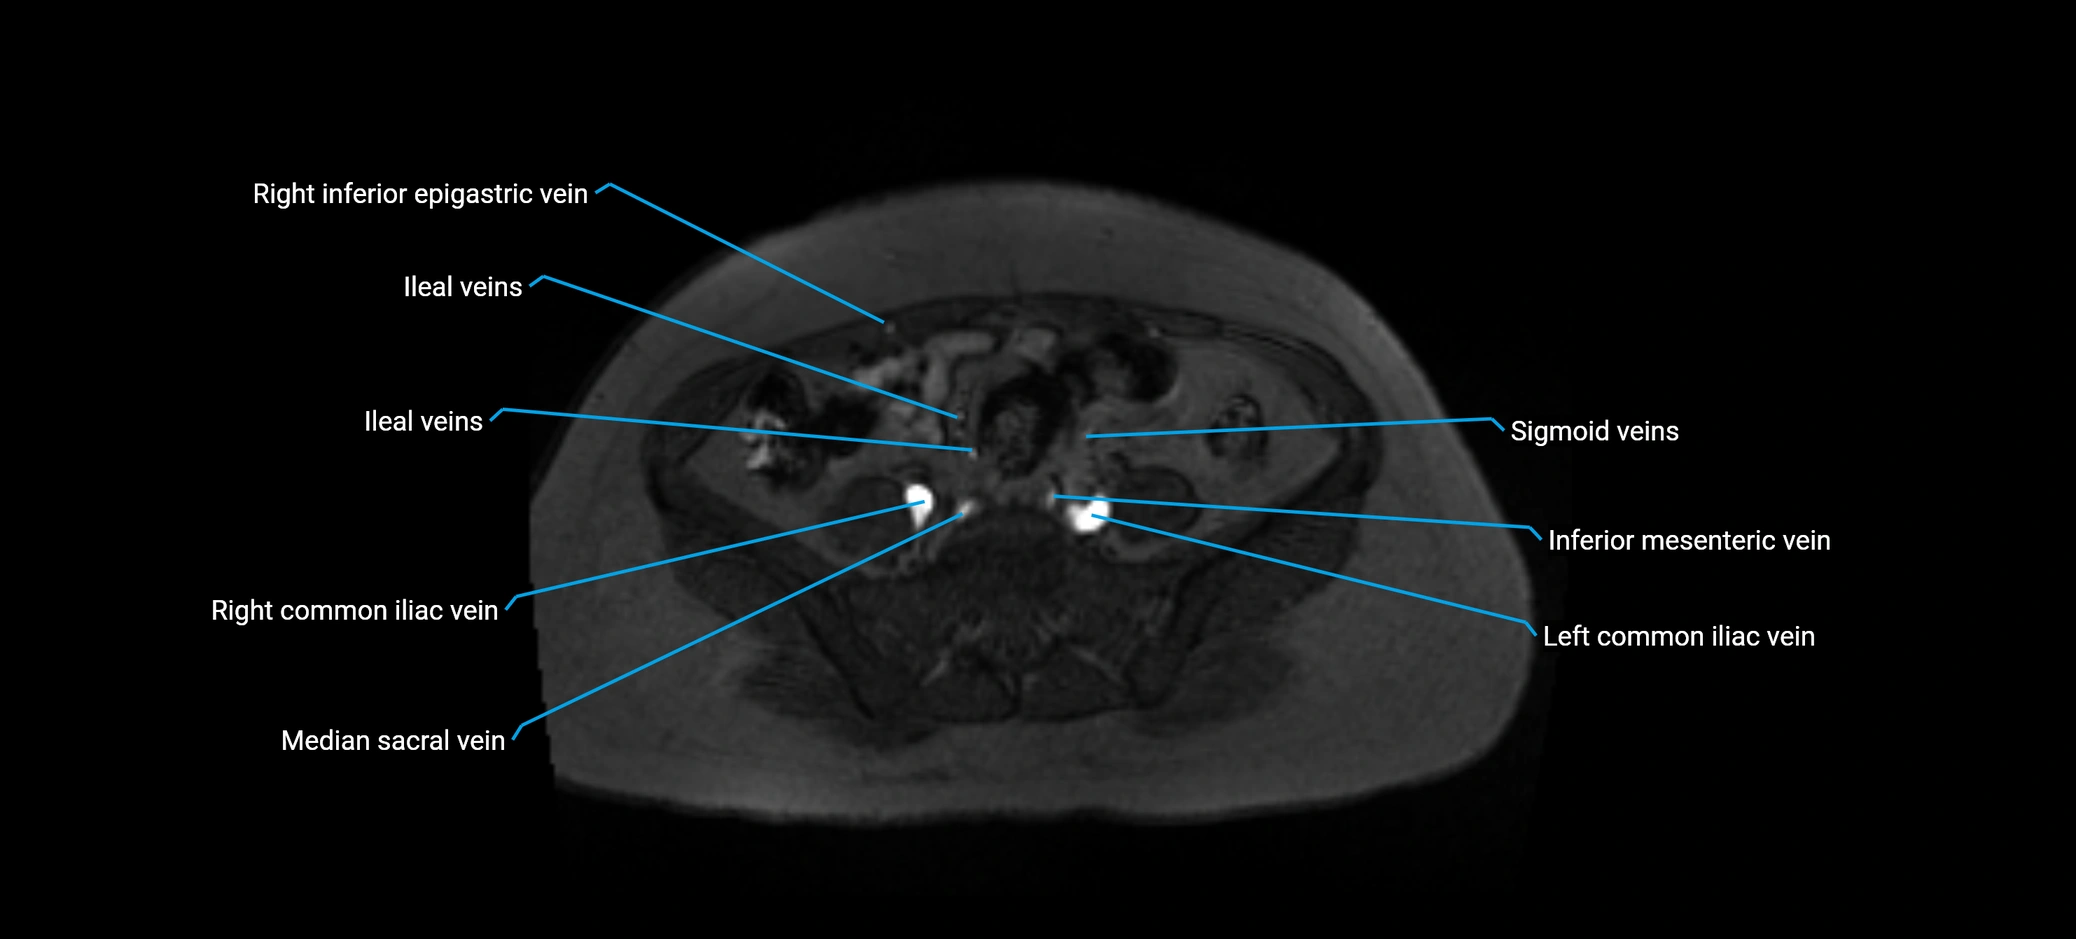

MRI image

image